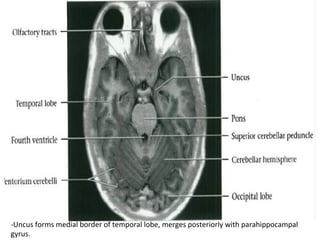

-Uncus	forms	medial	border	of	temporal	lobe,	merges	posteriorly	with	parahippocampal

gyrus.